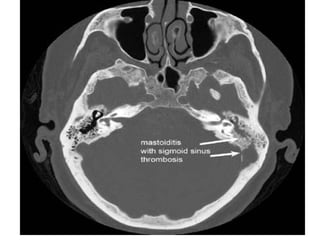

Mastoiditis.

Existe un absceso subperióstico, lateral, que puede afectar los espacios cervicales

(mastoiditis de Bezold).

Se encuentra como consecuencia de infección latente, puede aparecer pasadas dos

semanas del comienzo del cuadro de sobre infección de OMC.

•Otorrea

•Fiebre

•Dolor

•En 48% hay absceso retroauricular

•Son mas frecuentes en los niños que

en adultos.

•Necrosis parcial del conducto auditivo

externo.

•Dolor latente y una importante

exacerbación del mismo al presionar la

punta de la mastoides (signo de Caliceti)

•O el trago (signo de Vacher).

•Leucocitosis

Los exámenes radiológicos, será radiología simple (Shuller l) o TC, que permiten

apreciar la destrucción ósea.